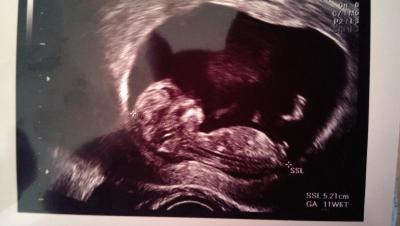

Hallo. Wollte mich auch mal wieder melden. Hatte heute endlich meinen zweiten frauenarzt Termin. Das mäuschen ist sogar schon 5 Tage weiter aber das ändert sich ja häufiger. Man konnte kaum ein Bild machen weil es so viel herrum gezappelt hat. So ist alles bestens. Anbei noch ein Bild meines hibbels

Bild zu 2 ultraschall - Forum für August - Mamis

Ne sind die Beine. Sieht aber wirklich auf dem Bild verdächtigt aus.

Ne wie gesagt ist das Bein. Von der seite ist denke etwas schwer den schnippel zu sehen da ja immer noch das Bein davor liegt. Bei meinem Sohn hatte ich nen Bild von unten.